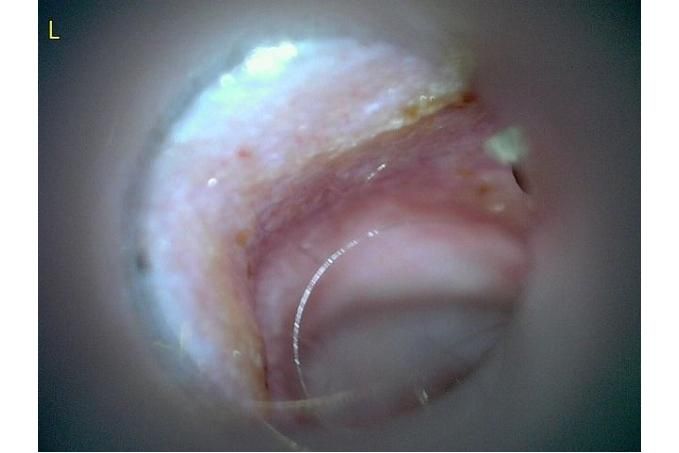

사진만 보고 확진할 수는 없지만 지금 올려주신 귀는 적어도 오른쪽은 정상으로 보이기 어렵습니다 왼쪽은 비교적 연분홍에 가까워 보이지만 오른쪽은 털과 분비물이 많이 차 있고 피부가 자극받은 듯한 모습이라 외이염 가능성을 먼저 생각하게 됩니다 그리고 질문자님이 적어주신 머리 털기 하루 여러 번 귀 만질 때 통증 솜만 닿아도 예민함 귀 긁기 같은 증상은 외이염에서 흔한 신호입니다

다만 이 사진만으로 중이염이나 내이염이라고 단정할 수는 없습니다 중이염이나 내이염은 귀 통증과 머리 털기만으로도 올 수 있지만 보통은 고개 기울어짐 비틀거림 안구가 흔들리는 증상 얼굴 한쪽 처짐 같은 더 깊은 신경 증상이 같이 보일 때 더 의심합니다 지금 적어주신 내용만 보면 제일 먼저는 오른쪽 외이도 염증과 통증 조절이 우선으로 보입니다

제 판단을 정리하면 지금 상태는 오른쪽 외이염 가능성이 높고 집에서는 알코올 세정제와 강한 귀세정은 잠시 멈추는 쪽이 더 안전합니다 그리고 약을 쓴다면 아무 귀약이 아니라 고막 확인과 세포검사 결과에 맞는 약이 필요합니다 질문자님처럼 이미 여러 말을 들어 혼란스러운 경우에는 기준을 하나로 잡으셔야 합니다 귀가 아픈 날에는 세정부터 하지 말고 먼저 통증과 염증을 가라앉힌 뒤 필요하면 부드럽게 청소하는 순서가 더 맞는 경우가 많습니다 하품은 귀 통증과 턱 주변 불편 때문에 같이 늘 수 있습니다

제가 드리고 싶은 한마디는 이겁니다 지금 귀는 아무것도 안 해도 되는 귀처럼 보이지는 않지만 집에서 이것저것 바꿔 넣어볼 귀도 아닙니다 오른쪽은 외이도 염증과 통증 쪽으로 보고 자극적인 세정은 피하면서 원인 확인 후 한 가지 치료로 정리하는 쪽이 맞아 보입니다